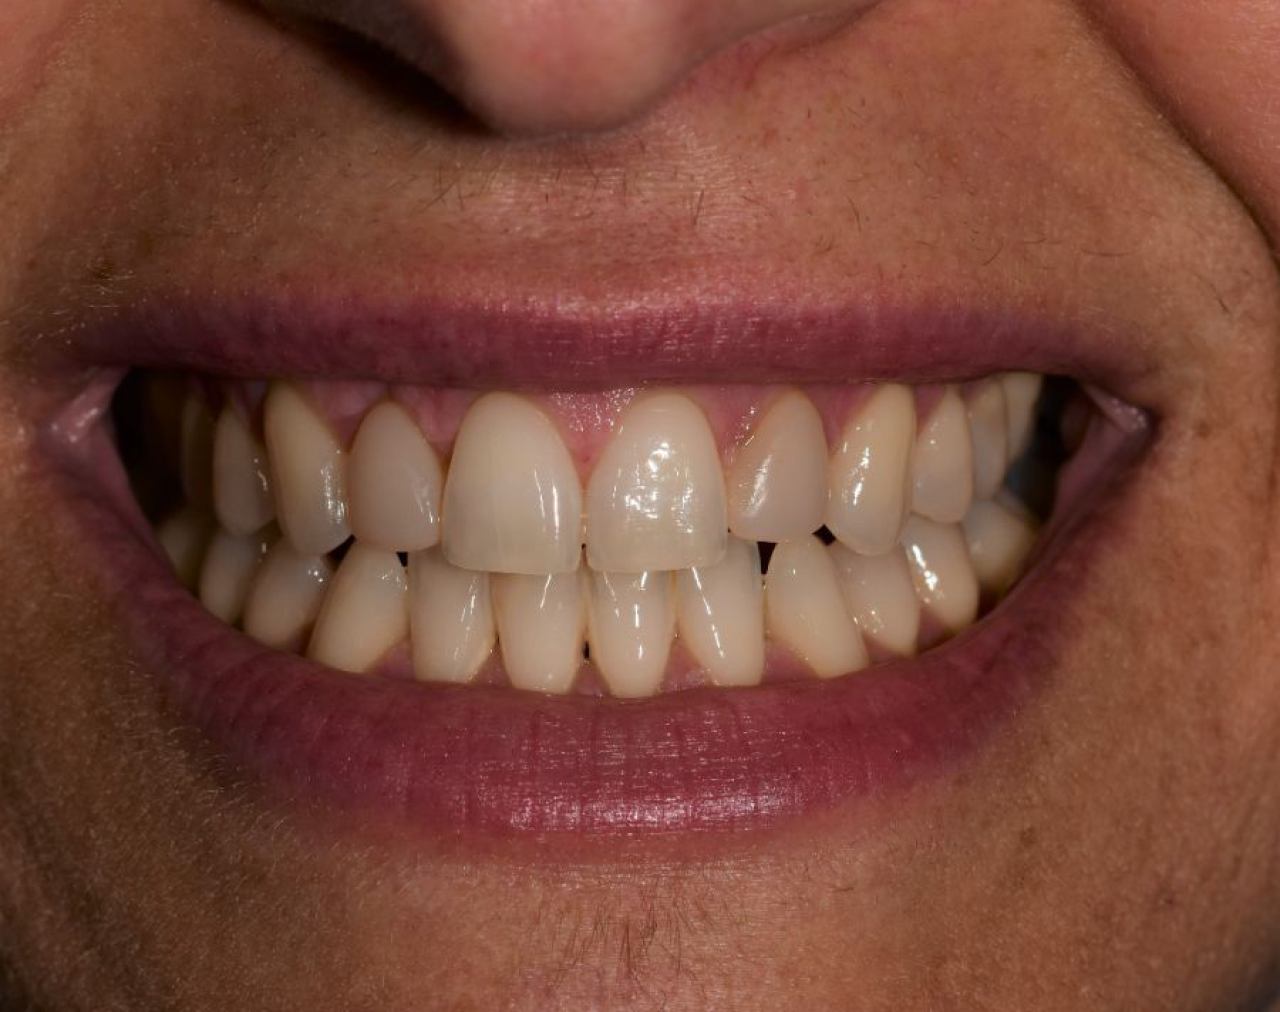

Ortodoncija

Digitalna ortodoncija uz nevidljivi aparatić postala je hit prije 10-ak godina u Sjedinjenim Američkim Državama. Marković Dental Clinic koristi se digitalnom ortodoncijom uz pomoć intraoralnog skenera i software-a, te se isporučuju prozirni aligneri(udlage) koje je potrebno mijenjati svaka 2 tjedna.